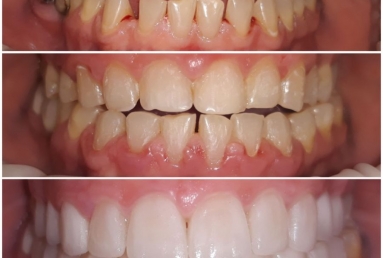

orthodontic treatment, full ceramic crowns

Our patient had general dental abrasion due to maloclusion. After orthodontic treatment, the upper teeth received full ceramic crowns, while the lower were restored with crowns and veneers.

We managed to solve partialy the orthodontic problem and at the same time restore the frontal teeth with esthetic ceramics for a perfect smile.